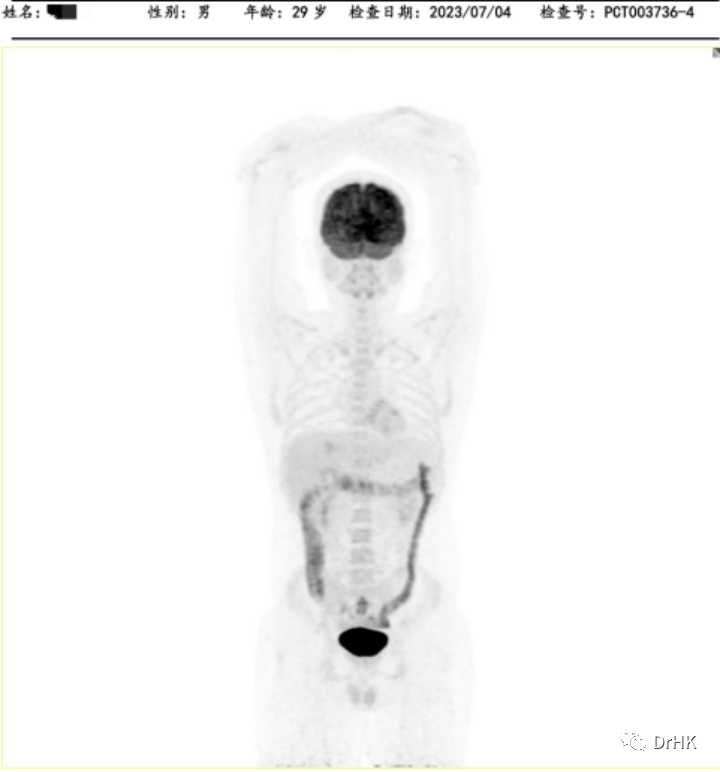

Starting from April 2, 2022, the patient was treated with the DA-TEDDi-R regimen combined with targeted therapy (ibrutinib + rituximab + dexamethasone + liposomal doxorubicin + etoposide + temozolomide + long-acting GCS + intrathecal Ara-C) for two cycles. After the treatment, the PET-CT assessment showed complete metabolic remission (the first complete remission since the onset of the disease), with a Deauville score of 2-3. Comparing this with the PET/CT imaging from our center on April 1, 2022, the liver lesion significantly decreased and the high metabolic activity disappeared; the left gluteus maximus lesion also disappeared. There were localized bone resorption and destructive changes in multiple bones (bilateral scapulae, clavicles, ribs, sternum, pelvic bones, and vertebrae), with some areas showing increased bone density, particularly in the left iliac bone. The bone marrow glucose metabolism was diffusely elevated, suggesting reactive changes post-treatment, and we recommended further evaluation with a bone marrow biopsy.

After achieving the first treatment goal, we proceeded with the second autologous transplantation combined with CAR-T cell therapy as a consolidation treatment. This time, we used the TEAM regimen for conditioning (tirofiban + etoposide + cytarabine + mafosfamide) and prepared and infused CD19/CD20 dual-target CAR-T cells. The treatment process was relatively smooth. After the CAR-T cell infusion, the patient started experiencing fever on day 5, with a peak temperature of 39°C on day 8. This was diagnosed as cytokine release syndrome (CRS), classified as grade I, with no signs of immune effector cell-associated neurotoxicity syndrome (ICANS). CAR-T cell expansion was detected, and the patient's granulocytes engrafted on day 14 (July 5, 2022) after autologous hematopoietic stem cell infusion, and platelets engrafted on day 12 (July 3, 2022) after the same infusion. After the transplant, the patient was given oral ibrutinib as maintenance therapy.

5. Follow-up

The patient was subsequently followed up regularly, with imaging evaluations completed six months and one year after the transplant. It is gratifying to report that the patient has maintained complete remission throughout this period. The PET images are shown below:

Six-Month Post-Transplant Imaging Evaluation

One-Year Post-Transplant Imaging Evaluation